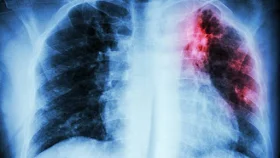

Una de las secuelas que podría dejar el covid-19 es la fibrosis pulmonar, una enfermedad que se caracteriza por el endurecimiento de las paredes de los pulmones y que dificulta su buen funcionamiento.